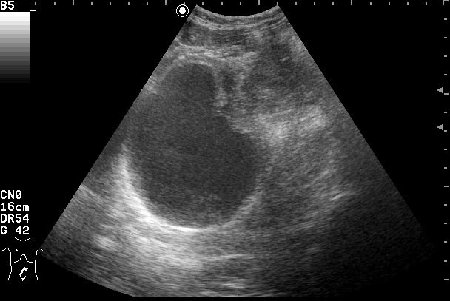

Пациентке была выполнена биопсия образования, назначена антибактериальная и противовоспалительная терапия.

Клиническое выздоровление через 2 недели. Сонограммы мочевого пузыря через 6 недель:

Если бы это было воспаление кисты, то мы бы видели изначально кисту с акустически непрозрачным содержимым. После лечения мы бы видели кисту с анэхогенным содержимым.zubr писал(а):У Митькова аналогичное образование названо воспаление кисты урахуса,что в принципе суть не меняет,а предполагает аналогичную тактику.